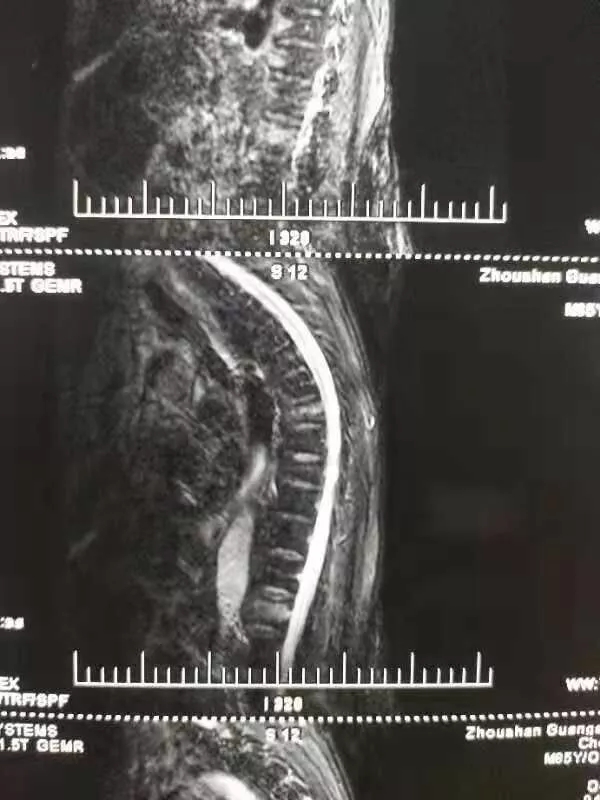

陳爺爺23日被家人送到我院門診,門診MRI、X片等檢查后,檢查結(jié)果為“腰1椎椎體壓縮性骨折”,門診在對癥處理后以“腰1椎體壓縮性骨折”將老人收入脊柱科。

進(jìn)行完善的檢查,脊柱科對老人病情確診如下:胸7、腰1椎體壓縮性骨折,重度骨質(zhì)疏松癥。